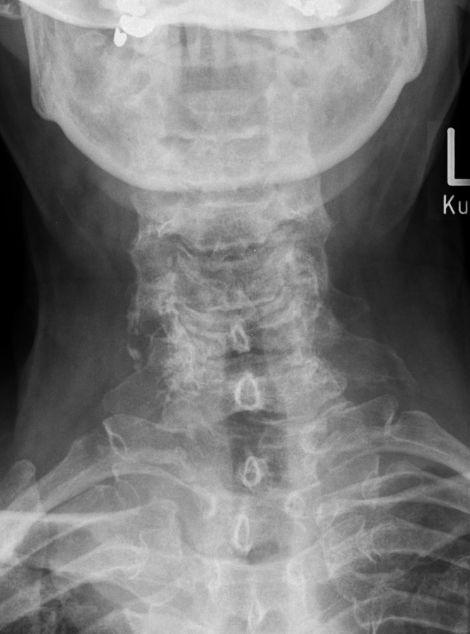

63-jähriger Mann mit multiplem Myelom Stadium IIIA.

Stabilitätsgefährdende Lysre in 6 und 7.![]() | |